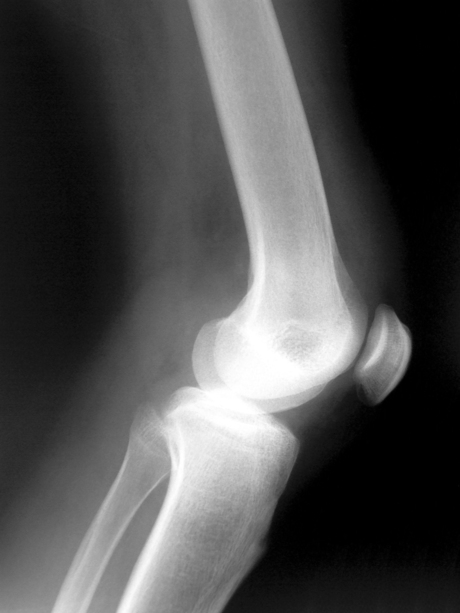

Stem cell trial for knee osteoarthritis underway

Regeneus (ASX:RGS) shares jumped over 20% today as the regenerative medicine company announced the first patient to be treated by Progenza, its mesenchymal stem cell (MSC) therapy treatment for knee osteoarthritis.

The patient was the first of 20 participants in the STEP (Safety, Tolerability and Efficacy of Progenza) clinical trial. The primary objective of the trial is to evaluate the safety and tolerability of Progenza, while the secondary objectives are to investigate the effect of the product over 12 months.

The stem cells in Progenza are sourced from adipose tissue, which is readily available and can be sourced in large initial quantities — the company has already demonstrated the capacity to produce over 10 million therapeutic doses of Progenza from a single donor. When Progenza cells are injected into a damaged joint or tissue, the MSCs have the potential to reduce pain and inflammation and slow the progression of the disease.

As a review of the sentinel patient’s safety data by the STEP safety oversight committee identified no safety concerns, enrolment in trial is now open to the remainder of the first cohort of 10 patients. A second and final cohort will receive a higher dose of cells.